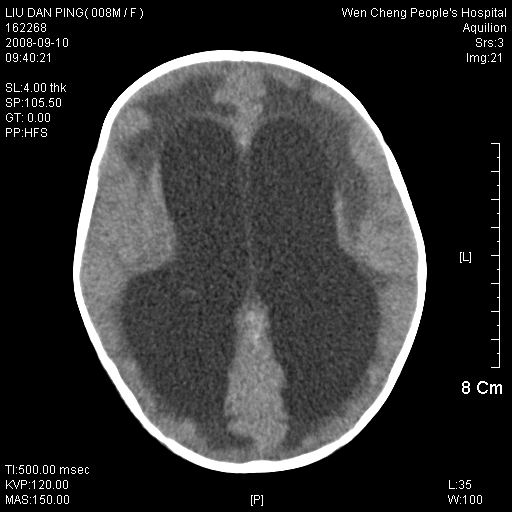

以下是引用卜一在2008-9-10 16:21:00的发言:[br]髓母细胞瘤伴梗阻性脑积水!支持![br]髓母细胞瘤特点:—般直径大于3.5cm,位于后颅凹中线之小脑蚓部。累及上蚓部的肿瘤延伸到小脑幕切迹之上,ct平扫肿瘤多呈均匀一致的高或等密度病灶,增强检查呈均匀一致的强化。病灶中有小坏死时,平扫亦可呈不均匀之混杂密度,注药后有增强。[br]

以下是引用zjzjr在2008-9-10 15:09:00的发言:[br]髓母细胞瘤伴梗阻性脑积水.